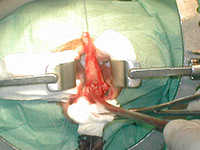

Буккальная 1 этапная уретропластика – Фотогалерея